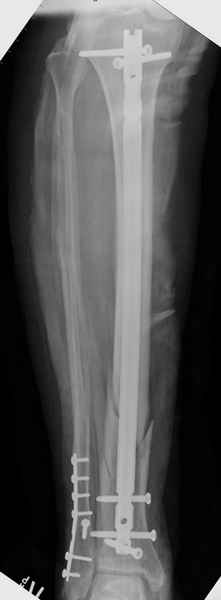

Здесь мы использовали новый Synthes Nail с дополнительными дырками, в проксимальной части 4: по две косых и поперечные (один стандартный а другой динамический), в дистальной части две поперечные, прямая и косая. Вес больного более 120 кг, нагрузку начнем через месяц.

Получилось красиво, поздравляю. Вверху можно было ограничиться одним винтом во фронтальное статическое отверстие, зачем два 45-градусных?

При такий спирали задний край tibia может быть сломан - нет ли этого в данном случае? На всякий случай можно было ввести 1-2 винта 4,5 мм спереди назад мимо гвоздя. Хотя самый дистальный блокирующий винт, возможно, зацепил этот отломок. А какой тут диаметр гвоздя и locking винтов?